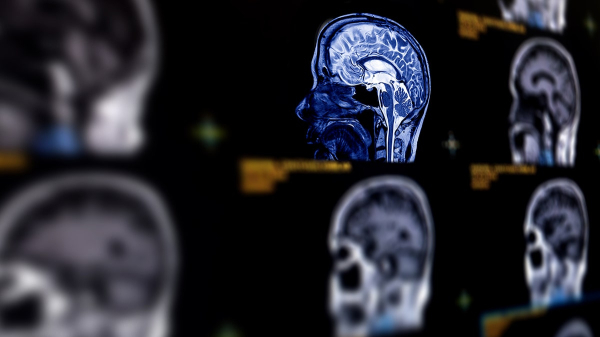

The Skims founder, 45, announced in a preview clip of Season 7 of Hulu’s “The Kardashians” that her doctors discovered the condition during an MRI scan, telling her family, “There was a little aneurysm.”

A brain aneurysm is the ballooning of a blood vessel in the brain, which can leak or rupture, leading to bleeding, according to Mayo Clinic.

Knowing the family history for aneurysms is important, Arthur added, as it’s recommended to get a screening exam, or MRI, if two relatives have had them.